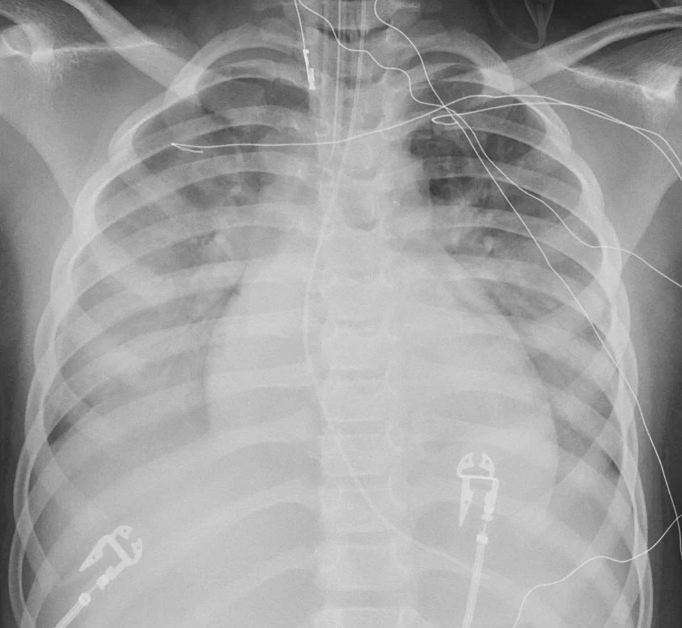

Dr. Karen Ramirez with her great takeaway: Horseshoe lung, pulmonary sequestration and congenital diaphragmatic hernia are common extracardiac symptoms in patients with Scimitar syndrome